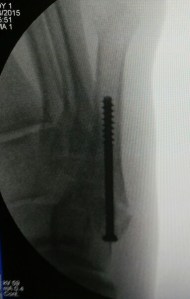

This is the final result:

The patient was able to bear weight on the right foot and walk by the 2nd week after surgery.